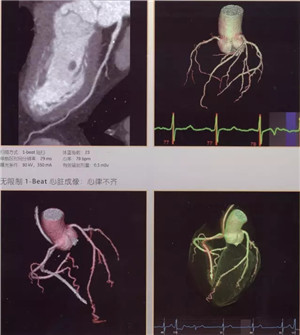

扫描速度超快:仅需0.28秒,不受心率快慢限制,只需一个心跳即完成精准的心脏CT检查,成为无创确诊冠心病的最佳检查手段。